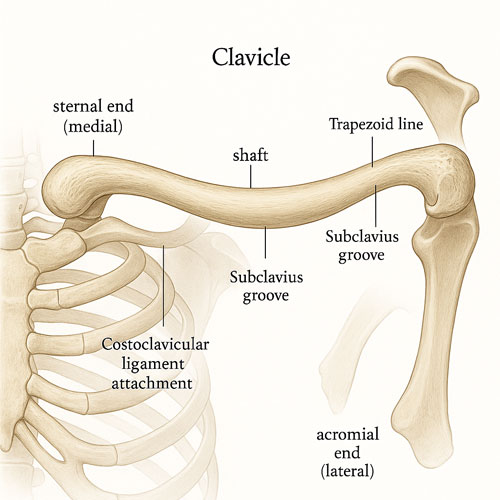

نقش و ساختار ترقوه

استخوان ترقوه یکی از معدود استخوان هایی است که از دوران نوزادی به طور کامل شکل می گیرد و مانند یک پل، شانه را به مرکز بدن متصل می کند. این استخوان با طول متوسط حدود پانزده سانتی متر، در دو سمت بدن قرار دارد و به کمک مفصل های شانه و جناغ، حرکت آزادانه بازوها را ممکن می سازد. ترقوه علاوه بر پشتیبانی مکانیکی، وظیفه محافظت از اعصاب و عروق مهمی را دارد که از بخش بالایی قفسه سینه عبور می کنند. طراحی منحنی و نازک آن باعث می شود هم انعطاف پذیر باشد و هم متأسفانه در برابر ضربه مستقیم یا فشار زیاد آسیب پذیر شود. عملکرد صحیح این استخوان برای تعادل شانه، قدرت حرکتی و جلوگیری از افتادگی شانه حیاتی است. هر گونه شکستگی یا آسیب شانه در این بخش، می تواند زندگی روزمره فرد را برای هفته ها یا حتی ماه ها مختل کند.